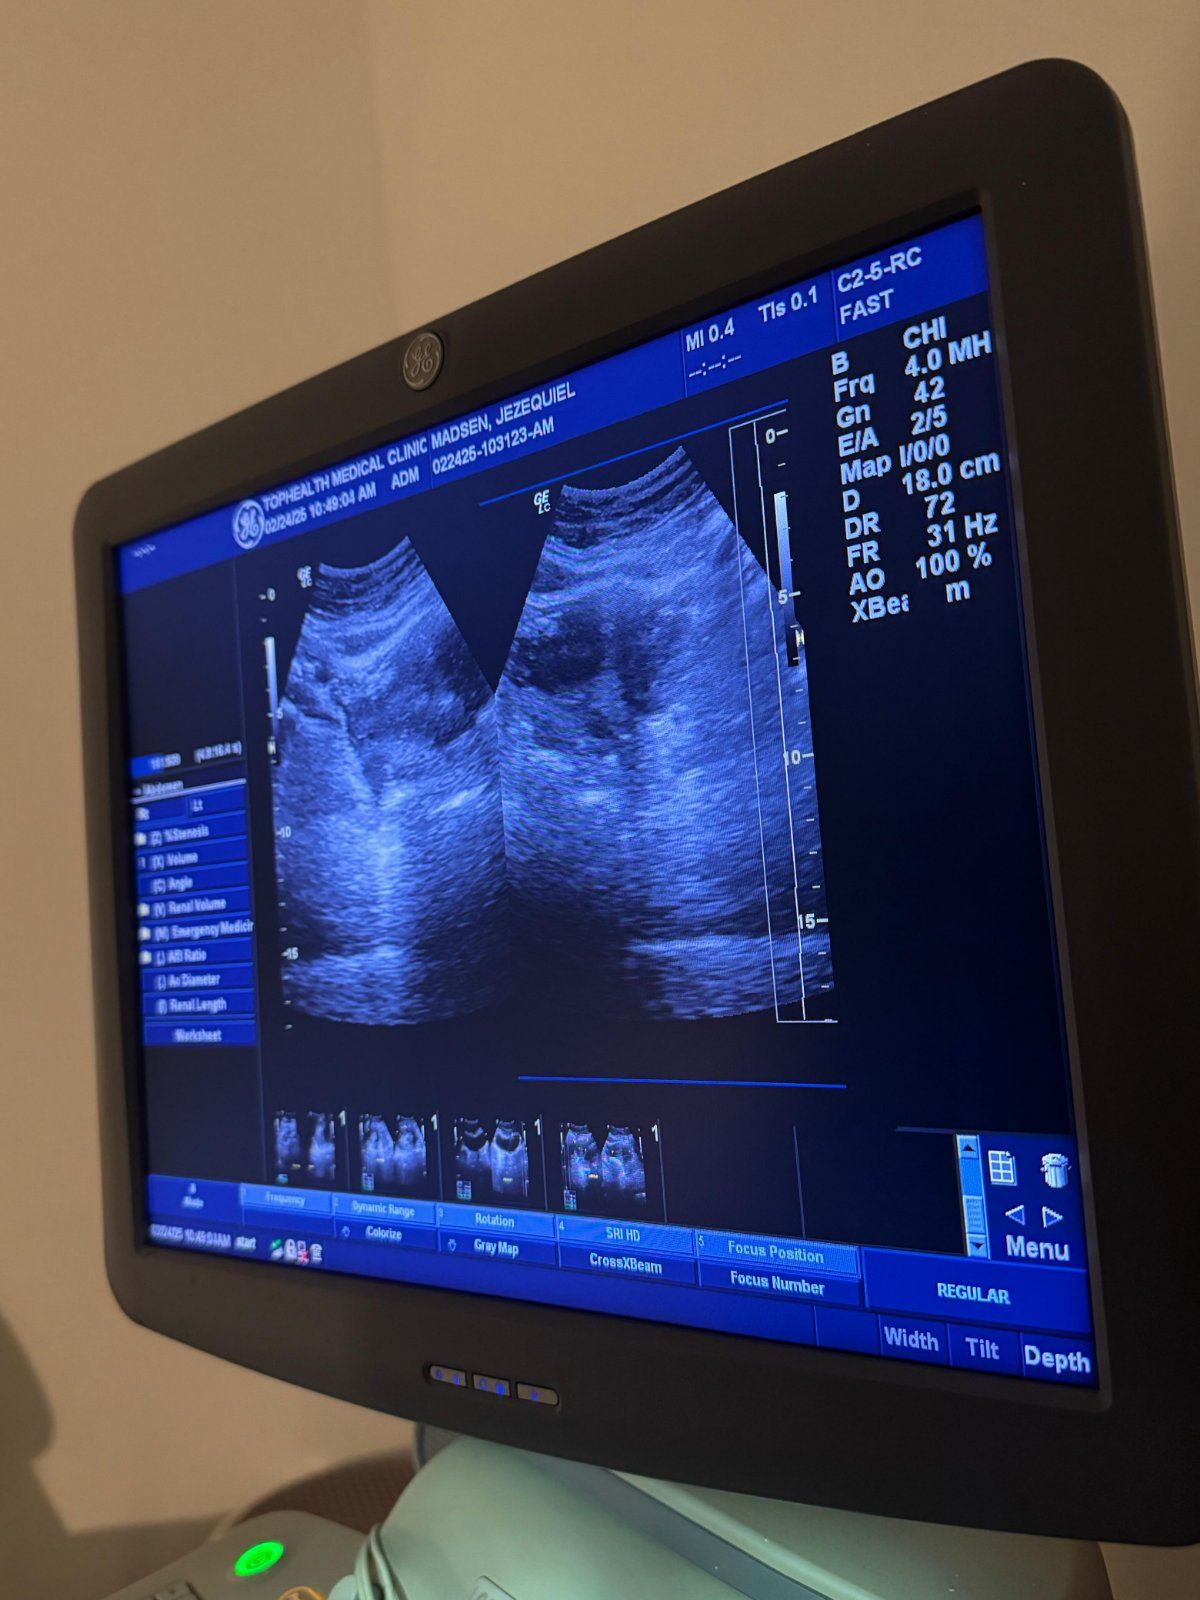

"We are most proud of having a wide range of diagnostic tests always ready to be performed for walk-ins from 8 a.m. to 9 p.m. This provides the highest level of convenience to our patients," explains Daniel, citing how TopHealth makes it easier for people to address health concerns. "We also work with the latest technology in Ultrasound, X-ray, and our new equipment for TopHealth derma center, that offers aesthetic procedures with CO2 laser, Diode laser, Q laser, and HIFU."